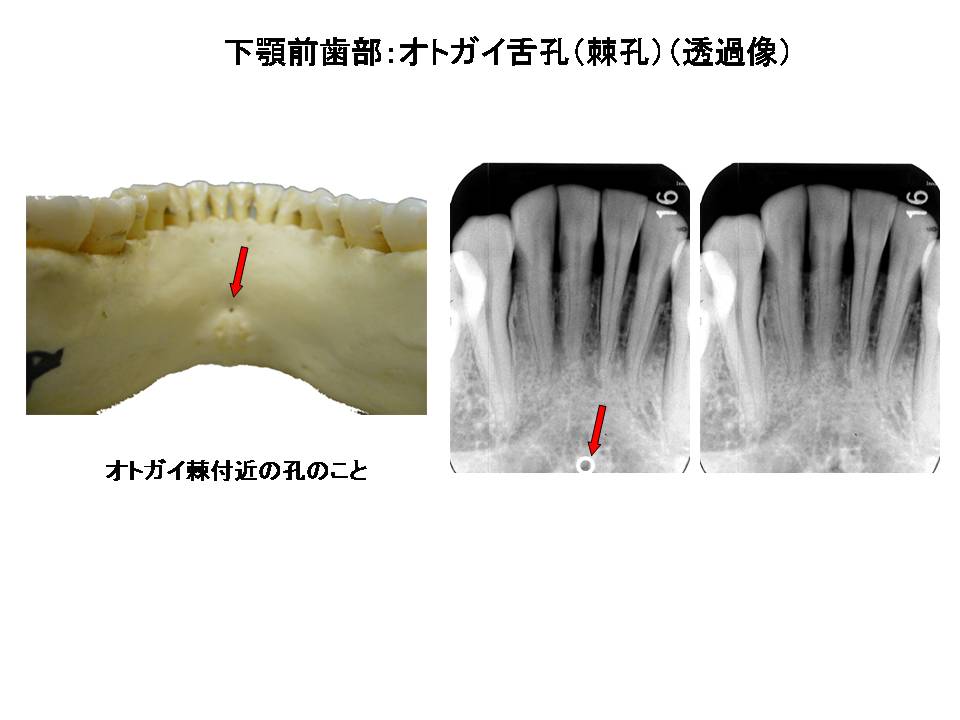

口内法(二等分法・咬合法)撮影の解剖